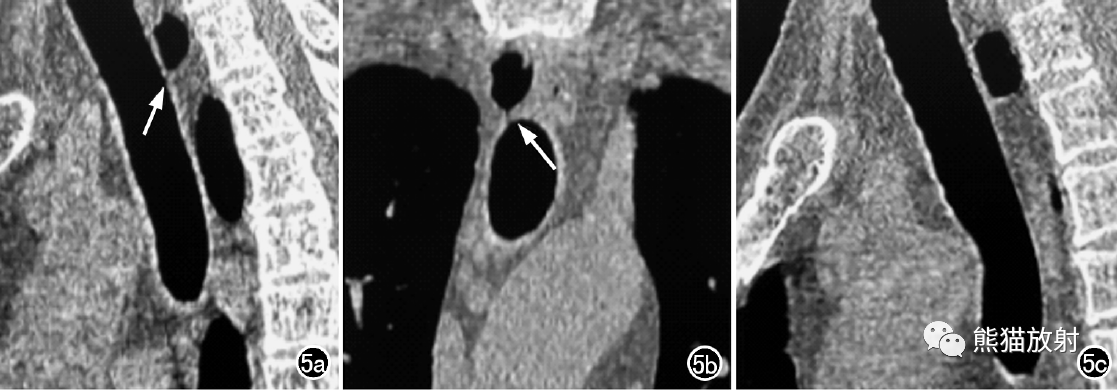

男,57岁。a)首次CT检查胸部矢状面MPR示TD下极纤细,充气AFDT向下倾斜,气管壁入口位于T2近下缘水平(箭),TD较小,位置较高,位于T1/2水平,气管稍有屈曲;b)冠状面MPR图像示气管壁入口位于T2近下缘水平(箭);c)一年多后随访复查示充气AFDT向上倾斜,足侧方向与冠状面夹角>100°,气管壁入口位于T2近中部水平,TD较大,位置较低,位于T1/2水平以下,气管较直。